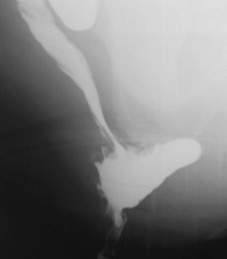

Дефекография, ректоцеле.

|

В отделении проводятся функциональные исследования желудочно-кишечного тракта: дефекография, прокто-резервуарография, исследование транзита по желудочно-кишечному тракту. Дефекография – рентгенологическая методика исследования анатомо-функционального состояния прямой кишки и тазового дна, имеющая важное значение для диагностики и определения программы хирургической коррекции таких заболеваний, как ректоцеле, наружное и внутреннее выпадение прямой кишки, дисфункция мышц тазового дна. ФГБУ «НМИЦ колопроктологии имени А.Н. Рыжих» Минздрава России является пионером этой методики в России и на сегодняшний день опыт отделения рентгенодиагностики составляет несколько тысяч пациентов, обследованных по этой методике.